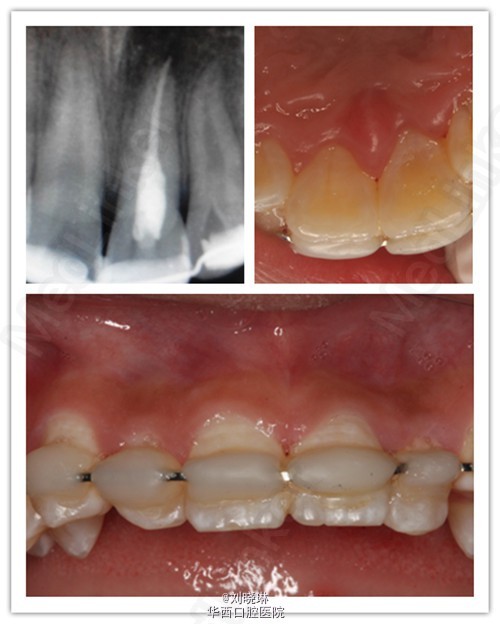

病人14岁,外伤导致上前牙脱落,患牙离体时间超过30小时。给患者讲明离体时间过长,患牙又未做正确方式保存,再植成功率低,患者要求试保留再植,术前签知情同意书。